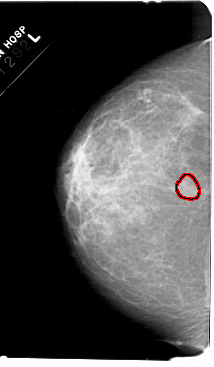

A_1607_1.RIGHT_CC

RIGHT_CC LINES 5491 PIXELS_PER_LINE 3241 BITS_PER_PIXEL 12 RESOLUTION 43.5 NON_OVERLAY

FILE: A_1607_1.LEFT_MLO.OVERLAY

TOTAL_ABNORMALITIES 1

ABNORMALITY 1

LESION_TYPE MASS SHAPE OVAL MARGINS OBSCURED

ASSESSMENT 3

SUBTLETY 2

PATHOLOGY BENIGN

TOTAL_OUTLINES 1

BOUNDARY